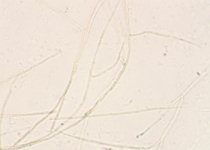

| Species Name: | Rhinocladiella mackenziei |

| Taxonomy: | FUNGI Ascomycota, Eurotiomycetes, Chaetothyriales, Herpotrichiellaceae |

| Substrate: | brain abscess, male originally from Somalia, 60 yr, DE+ |

| Characters: | HUMAN/ ANIMAL PATHOGEN cerebral phaeohyphomycosis - // THERMOTOLERANT grows @ 37C - (Click for publications citing UAMH 9926) |